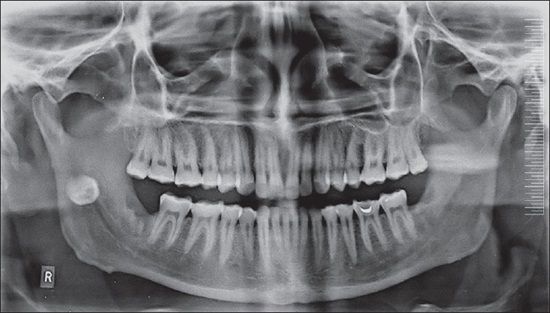

Ezt a fajta felvételt akkor kéri az orvos, ha általános kivizsgálásra érkezünk a fogászatra, vagy góckutatást szeretnénk. A „film” ilyenkor a szájüregen kívül helyezkedik el és az elkészült felvétel a teljes fogazatról ad képet a fogorvosnak. Segítségével nem csak előkészíthetők, de nagyobb precizitással el is végezhetők a szájsebészeti, parodontológiai műtétek, valamint a fogszabályozó szakorvos is igénybe veheti a tervezés során.

Fog panoráma röntgen segítségével tájékozódhatunk:

• a fogváltás utáni tinédzser fogak helyzetéről

• a gyökértömések állapotáról

• a gyökércsúcsi elváltozásokról

• egy betört foggyökér helyzetéről

• szuvasodásokról

• implantátumok helyzetéről

• a fogágy egészségéről

• gyulladások, ciszták kiterjedéséről

• a bölcsességfogak helyzetéről

A leggyakoribb páciens kérdés: A panoráma röntgenen mi látszik?

Intraorális röntgen és panoráma röntgen elemzése során is rábukkanhatunk gyanús, kezelésre szoruló fogakra.

Fogciszta röntgen felvételen:

A leggyakrabban általában a foggyökér csúcsa környékén fedezhetők fel a gócnak számító ciszták. A fogcisztának saját burka van, így a képeken élesebb határral rendelkező kisebb vagy nagyobb gombócnak tűnik.

A foggyökér gyulladás röntgen képe:

A gyulladás az egészséges csontszövettől sötétebb foltként jelenik meg, jellemzően szintén a gyökér körüli területen.